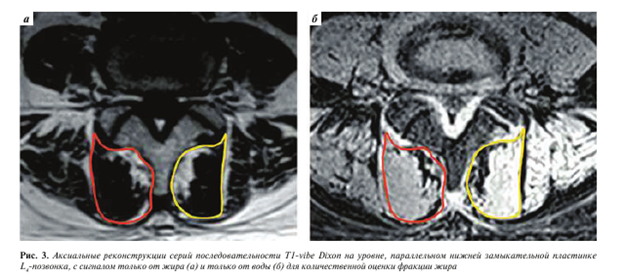

У пациентов, которым выполняли режим с методикой жироподавления Dixon, аналогичным образом измеряли интенсивность магнитно-резонансного сигнала на реконструированных сериях с сигналом только от жира (IF) и только от воды (IW) (рис. 3) для расчета показателя фракции жира (fat fraction, FF) по формуле FF = IF/(IW + IF), предложенного изначально для количественной оценки жирового замещения мышц у пациентов с миопатиями [11].